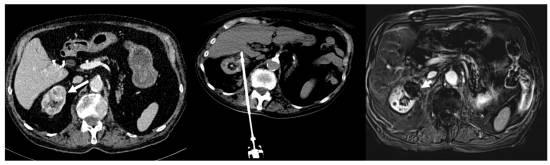

Caption: 85-year-old man with 3 cm biopsy-proven clear cell renal carcinoma (image left, white arrow)). RENAL nephrometry score calculated as 6. The central image shows the CT scan obtained with the patient in a prone position and the cryoprobe placed in the tumor with the final ice ball (end of the second freezing cycle). The right image shows the MRI during follow-up at 1 month, demonstrating complete local response with no evidence of tumor enhancement (white arrow head). |

The objective of this retrospective Study was to address the challenges of managing small renal masses, including recurrence rates, by exploring the safety and efficiency of single-probe percutaneous cryoablation as a potential solution. The causes of partial tumor response and persistent tumor residue after a T1a renal cryoablation procedure were assessed. A total of 25 patients underwent cryoablation for 26 T1a renal tumors with a median tumor size of 25.3 mm (20 to 30.7 mm) and a median RENAL nephrometry score, indicating tumor complexity, of 7 (5 to 9).